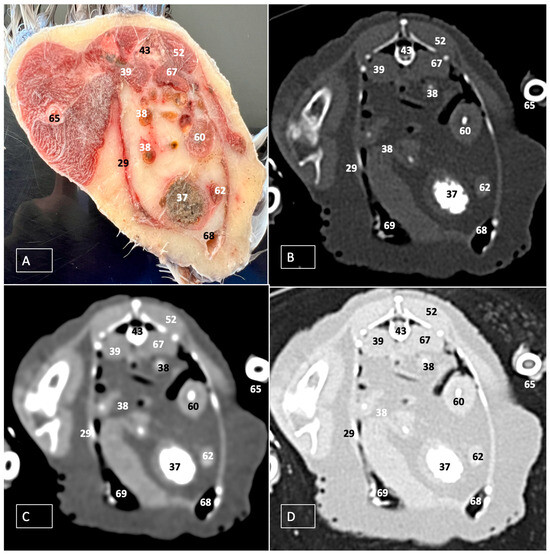

3.1. Anatomical Dissections and Cross-Sections

3.2. Computed Tomography Images